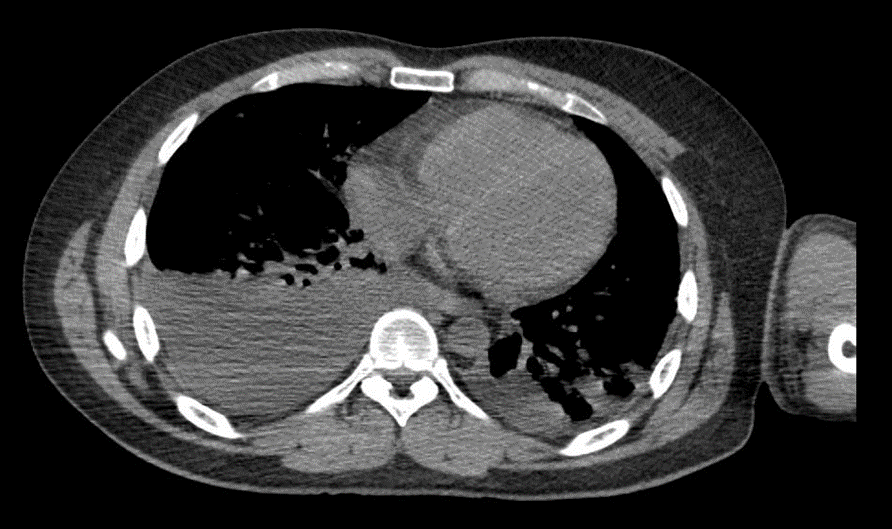

TC tórax (02/04/2025): Partes moles da parede torácica e arcabouço ósseo sem alterações. – Pequeno derrame pleural bilateral, associado a atelectasia compressiva do parênquima pulmonar adjacente. Atenuação habitual do restante do parênquima pulmonar. –

Traqueia, carina e brônquios principais pérvios, com situação, calibre e contornos normais. – Estruturas vasculares de aspecto preservado. Coração com situação, morfologia, contornos e dimensões normais. Ausência de linfonodomegalias mediastinais ou perihilares atípicas.

Figura 7: Tomografia Computadorizada de abdome.

ANGIOTC Tórax (03/04/25): Tronco da artéria pulmonar e ramos principais com calibres preservados, não se evidenciando falhas de enchimento até ramos subsegmentares. Aorta de calibre preservado, sem evidência de dissecção ou aneurisma. Demais estruturas vasculares mediastinais com trajeto e calibre preservados. Coração com dimensões normais. Pequeno derrame pleural bilateral, determinando atelectasia passiva. Focos consolidativos em lobos inferiores. Opacidades fibroatelectásicas esparsas em ambos os pulmões. (Após análise, descartado diagnóstico de TEP)

ANGIOTC de tórax 07/04/2025: Tronco da artéria pulmonar com calibre aumentado (3,3 cm). Ramos principais com calibres preservados, não se evidenciando falhas de enchimento até ramos segmentares. Demais estruturas vasculares mediastinais com trajeto e calibre preservados. Focos consolidativos e em vidro fosco esparsos bilateralmente, especialmente em lobos superiores e inferior esquerdo. Derrame pleural moderado à direita e pequeno à esquerda com atelectasia compressiva associada. Coração com dimensões normais. Não há linfonodomegalias mediastinais. Traqueia e brônquios principais pérvios, de calibres conservados. Espondilose torácica. (Após análise pela equipe da cirurgia torácica, realizada toracostomia com drenagem pleural a direita com saída imediata de 500ml de conteúdo hemático)

Figura 8: ANGIOTC de tórax.